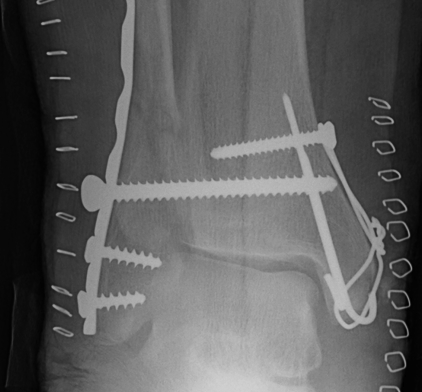

Fracture patterns

| Lateral malleolar fractures | Medial malleolar fractures | Bimalleolar fractures | Trimalleolar fractures |

Weber A - below syndesmosis Weber B - at syndesmosis Weber C - above syndesmosis |

Uncommon |

Fibular + medial malleolus Bimalleolar equivalent - fibular + deltoid ligament Fibular + posterior malleolus |

Fibular fracture + Medial malleolus fracture + Posterior malleolus fracture |